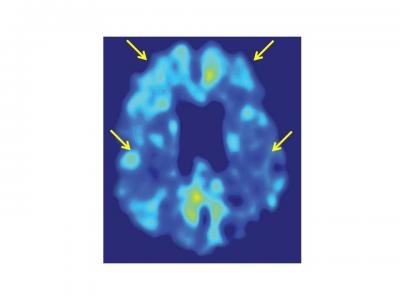

In addition, each participant was injected with a chemical marker called FDDNP, which binds to deposits of amyloid beta plaques and neurofibrillary tau tangles in the brain. The researchers then used positron emission tomography (PET) to image the brains of the subjects — a method that enabled them to pinpoint where these abnormal proteins accumulate.

The researchers also observed that FDDNP binding levels in the brain correlated with participants' cognitive performance. For example, volunteers who had greater difficulties with problem-solving and language displayed higher levels of the FDDNP marker in areas of their brain that control those cognitive activities.